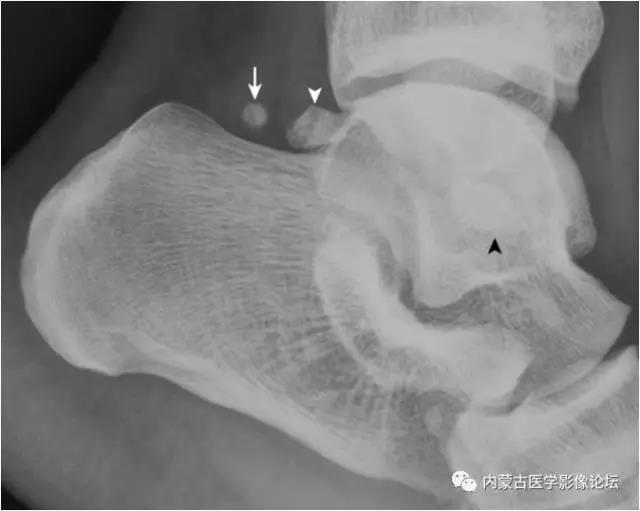

足正侧位x线正常图片,跟骨侧位x线解剖图

跟骨侧位x线解剖图

足侧位x线解剖图

足骨x线解剖图

跟骨正侧位x线解剖图